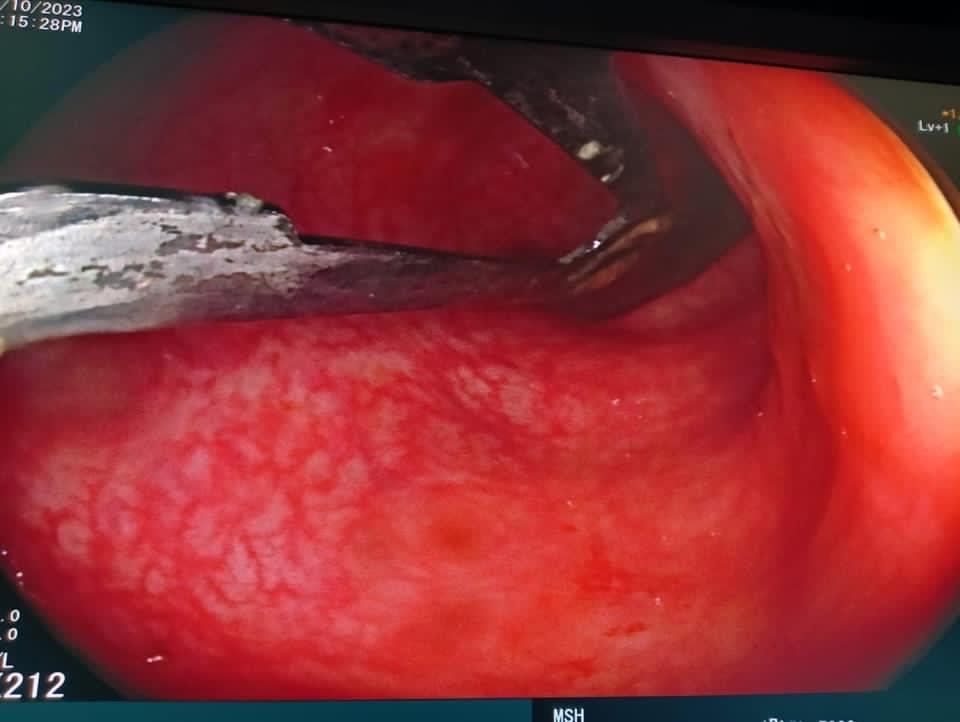

استخراج مشرط جراحي من داخل أمعاء فتاه بمستشفي المنصورة التخصصي

نجح فريق طبي بمستشفى المنصورة التخصصي التابعة لأمانة المراكز الطبية المتخصصة، من إجراء عملية نادرة بالمنظار الطبي لفتاة تعاني من اضطراب نفسي تبلغ من العمر 16 ابتلعت مشرط طبي، واستطاع فريق الجهاز الهضمي والمناظير بمستشفى المنصورة التخصصي، من استخراج المشرط الجراحي من داخل أمعائها باستخدام المنظار، ودون الحاجة إلى تدخل جراحي، والحالة بصحة جيدة وتم خروجها من المستشفى.

وضم الفريق الطبي دكتور منصور صقر استاذ مناظير الجهاز الهضمي، ودكتور أحمد حامد تخدير، وتمريض المناظير هبة عبد الحميد، وإيناس محمد سامي، وتمريض العمليات دنيا السيد المعداوي وأسامة جمال.